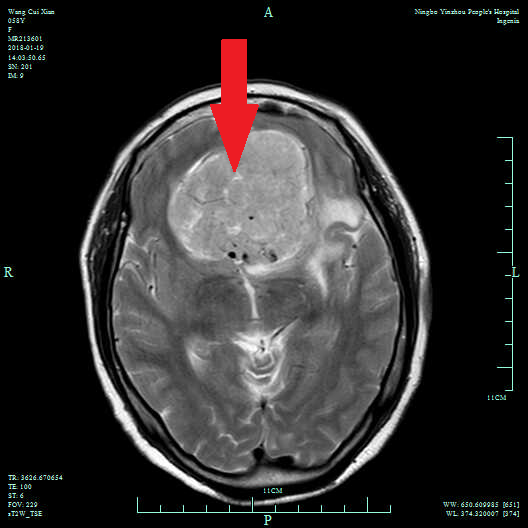

病人,女性,66岁,因“反应迟钝半年”入院,入院诊断嗅沟巨大脑膜瘤。

术前颅脑MRI增强,剪头提示嗅沟巨大脑膜瘤。